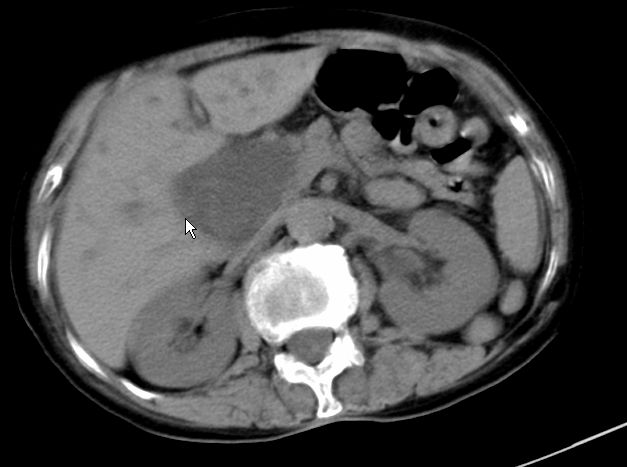

以下是引用zjzjr在2008-12-16 12:49:00的发言:[br]肝内外胆管全程扩张,胆囊明显增大,未见占位征像.建议mrcp.

以下是引用jiangjing在2008-12-16 13:19:00的发言:[br]肝内外胆管全程扩张,胆囊明显增大,扩张胆总管下段径较中上段小,未见胰管扩张,提示胆总管远端梗阻伴感染.建议增强及mrcp 检查

以下是引用朱亮在2008-12-16 12:54:00的发言:[br]胆总管远端应薄层扫描 胆总管逐渐变细 考虑胆系慢性炎症